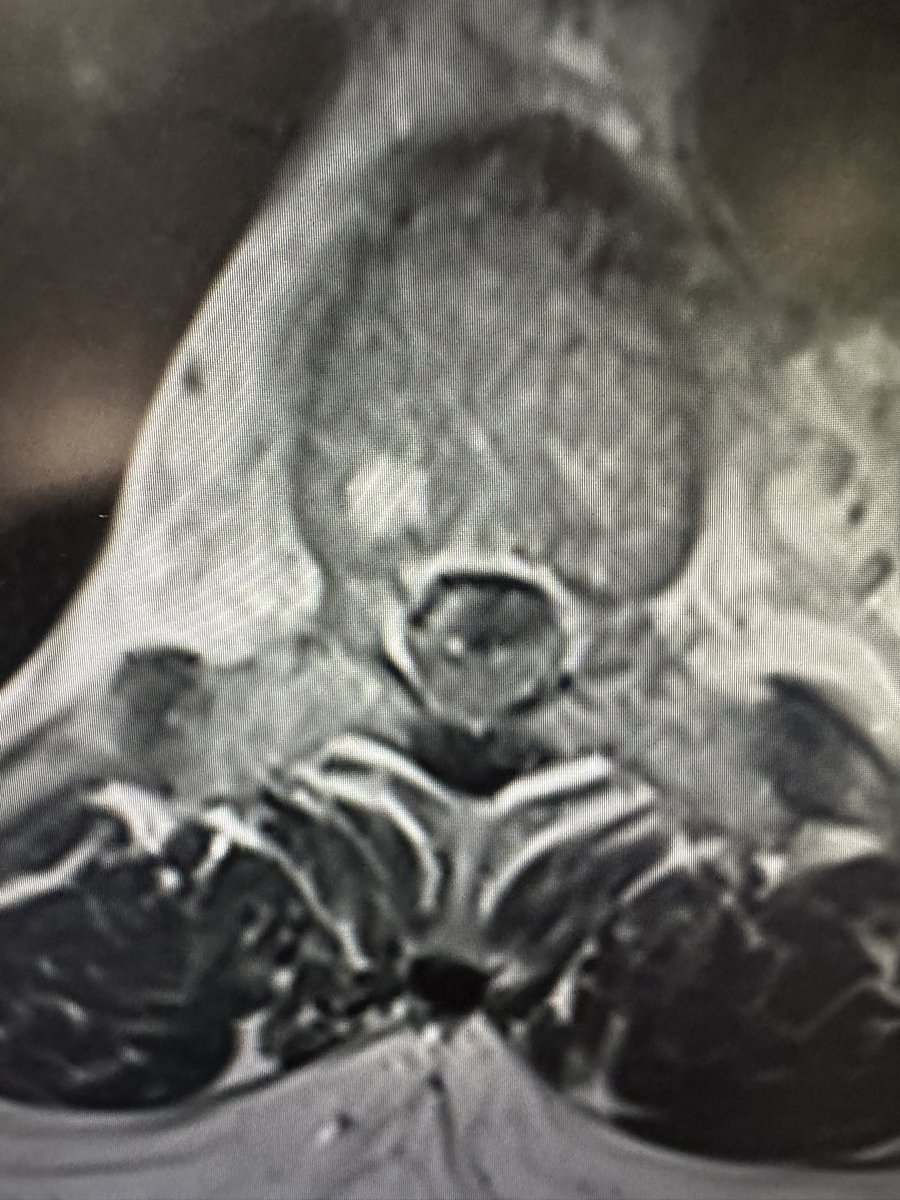

Ventral thoracic intradural tumors can be safely reached from a posterior approach with release of the dentate ligaments and drilling more of the facets. @emoryhealthcare @EmoryNeurosurg @spinesection